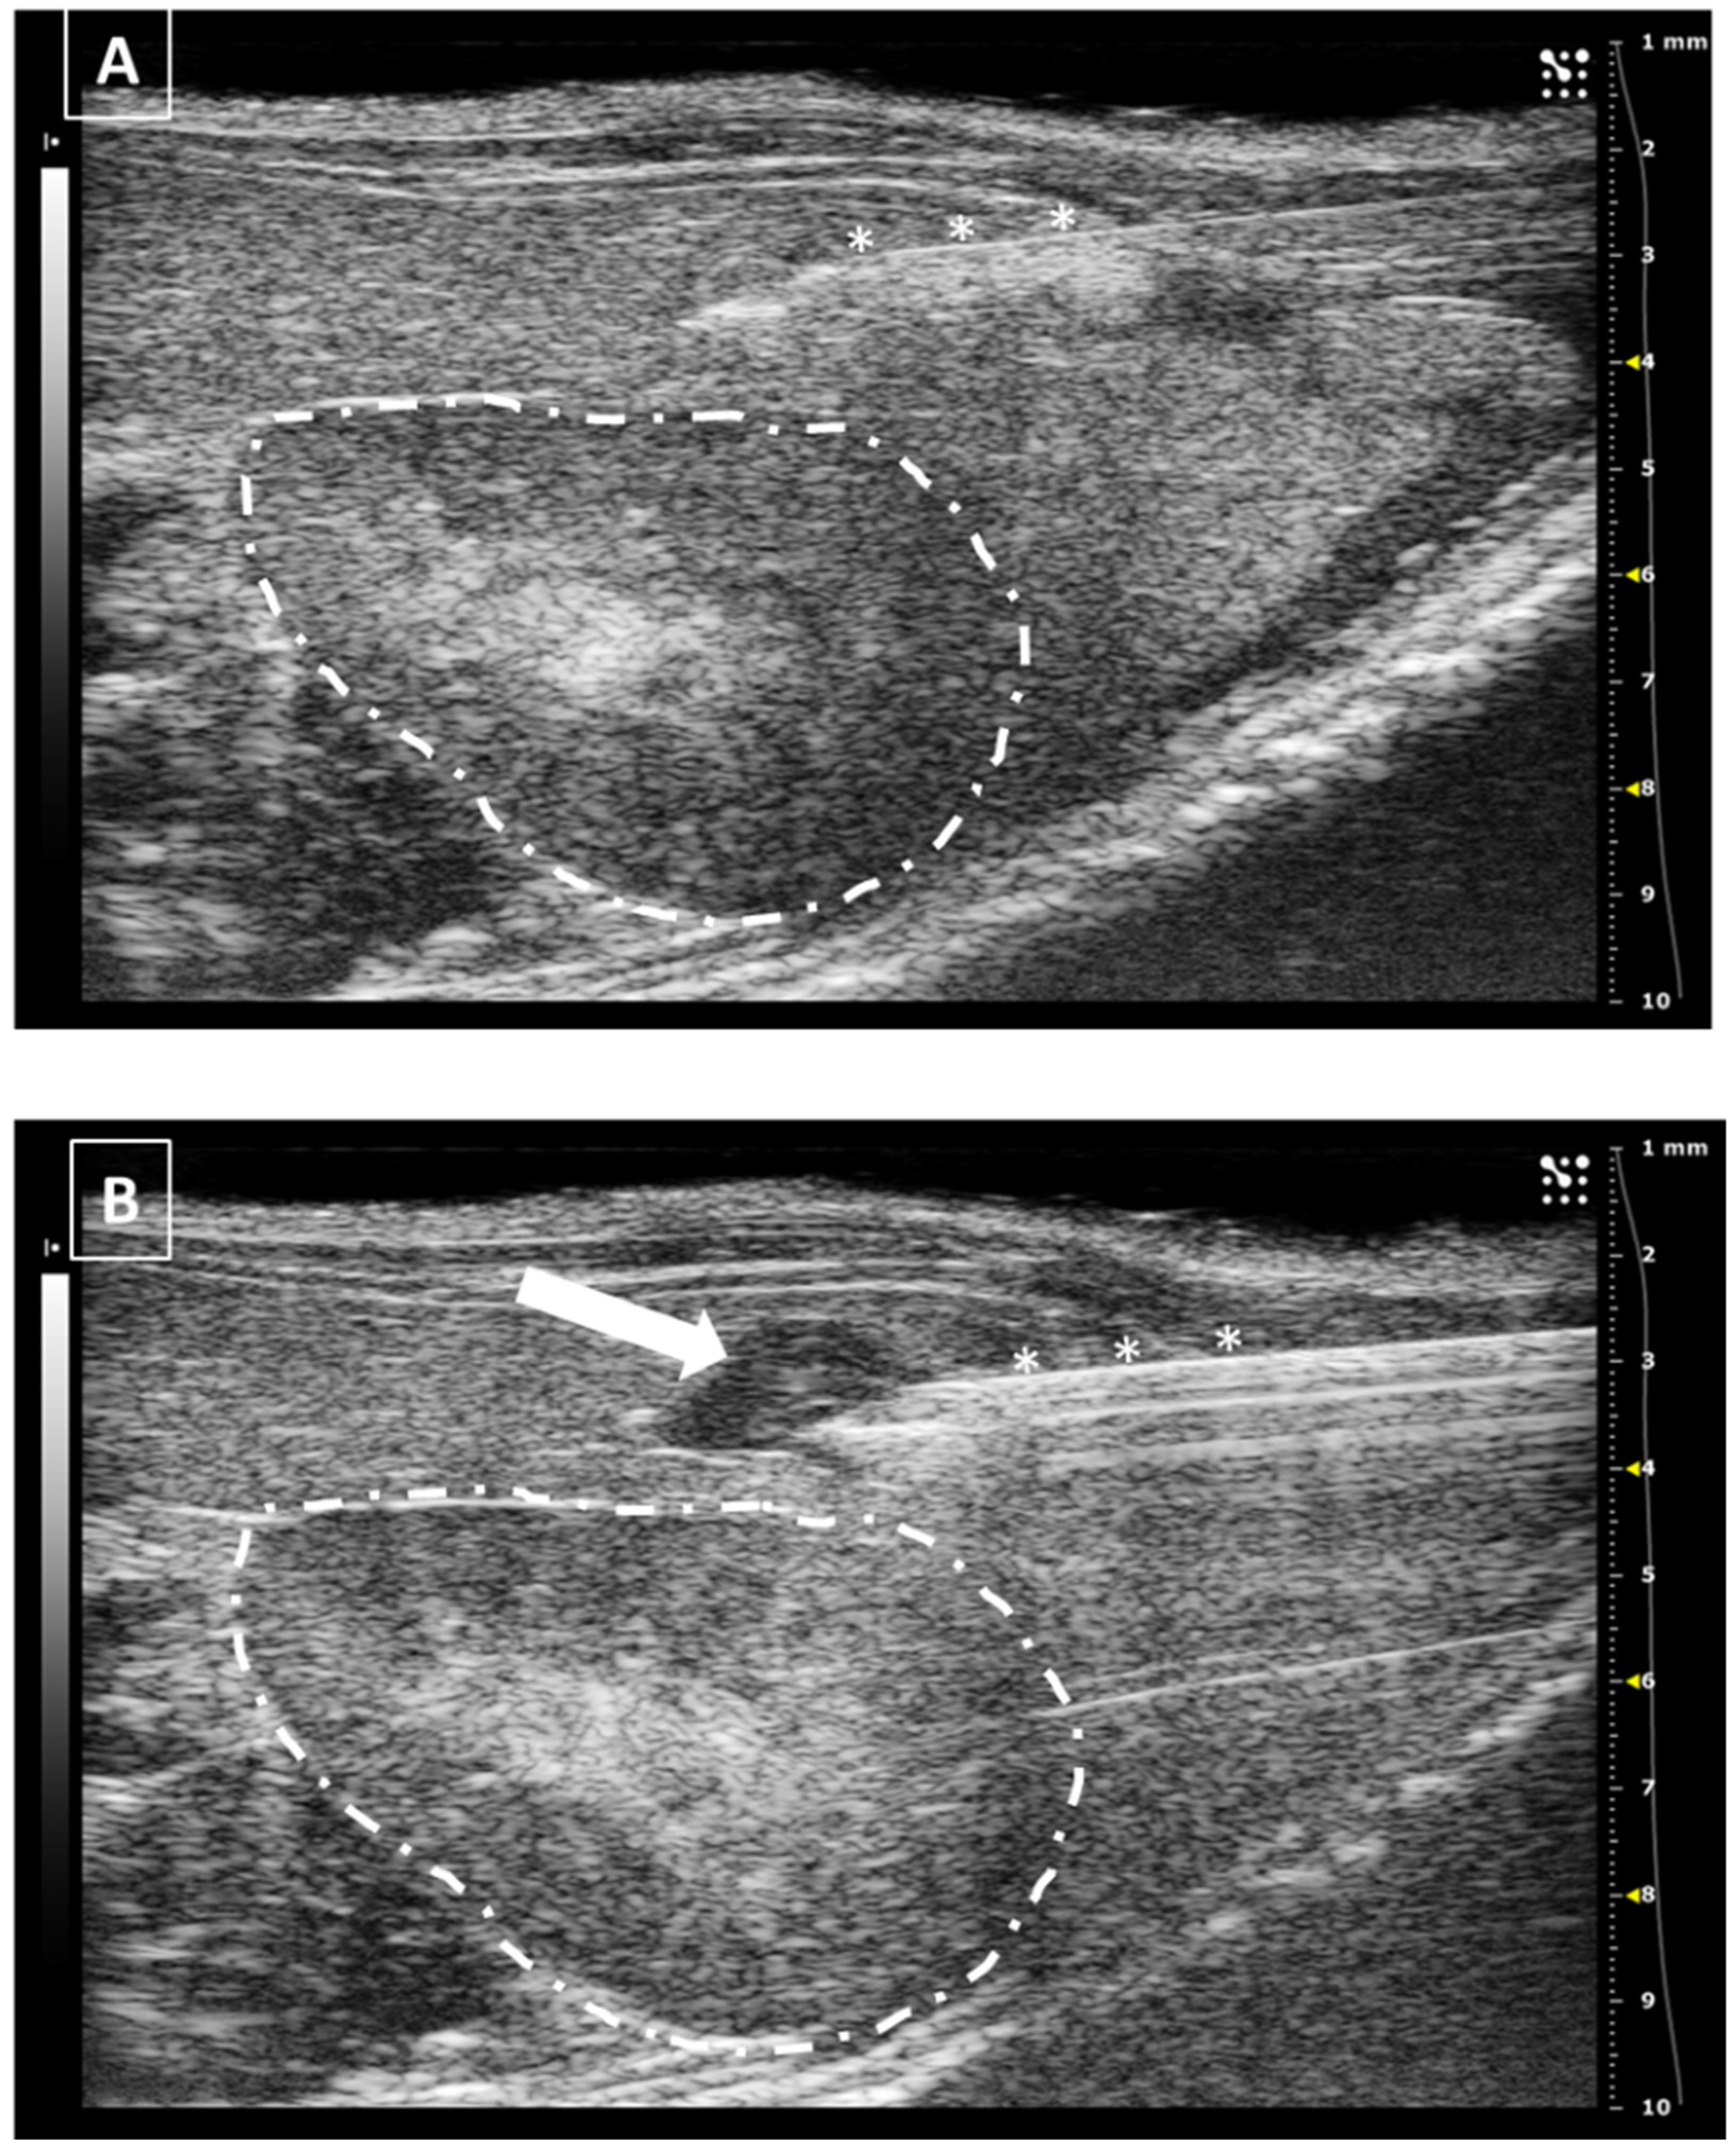

In the same way as the liver and spleen, the kidney biopsy can be performed following the same approach as the injection but pulling the needle plunger instead of pushing it down. Multiple samples can be collected in both the cortical and medullar areas of the organ. An example of a renal injection is shown in Figure 7.

The major risk during a renal injection is the incorrect settlement of the fluid. If the injection is performed too deeply into the renal tissue, the tip of the needle could reach the pelvic zone. In this case, the injected fluid will be released directly into the pelvic area and moved to the ureters. Another risk of incorrect injections could be injecting into the renal vessels, especially the renal vein, bigger than the artery. But this possibility is low if we make a safe approach from the lateral or dorsum.

Figure 7. Intrarenal injection. (A) Injection of the needle into the kidney. Needle is marked with white asterisks and the kidney is surrounded by a dashed line. The injection is performed in the medullar zone of the organ. (B) Administration of the fluid, that is marked with a white asterisk. Images obtained at 40 MHz frequency.